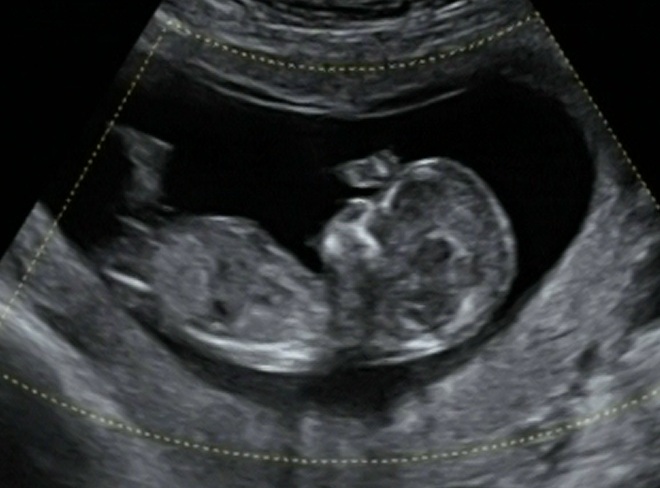

I think boy.

I think girl but I am new at this.

Girl

I'm guessing GIRL :D

I would guess girl.

Great video, your bubba is so cute, i think i saw boy parts from the potty shot at the start though, i have to change my guess.